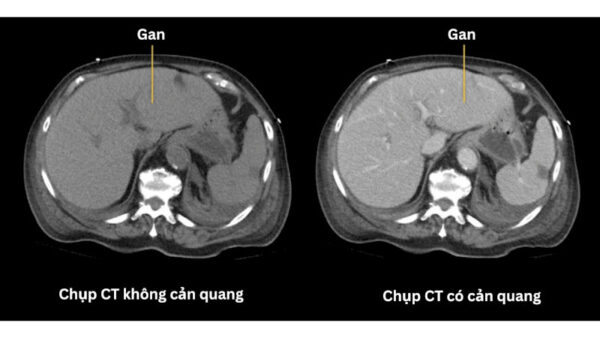

4. An toàn hơn so với CT có cản quang